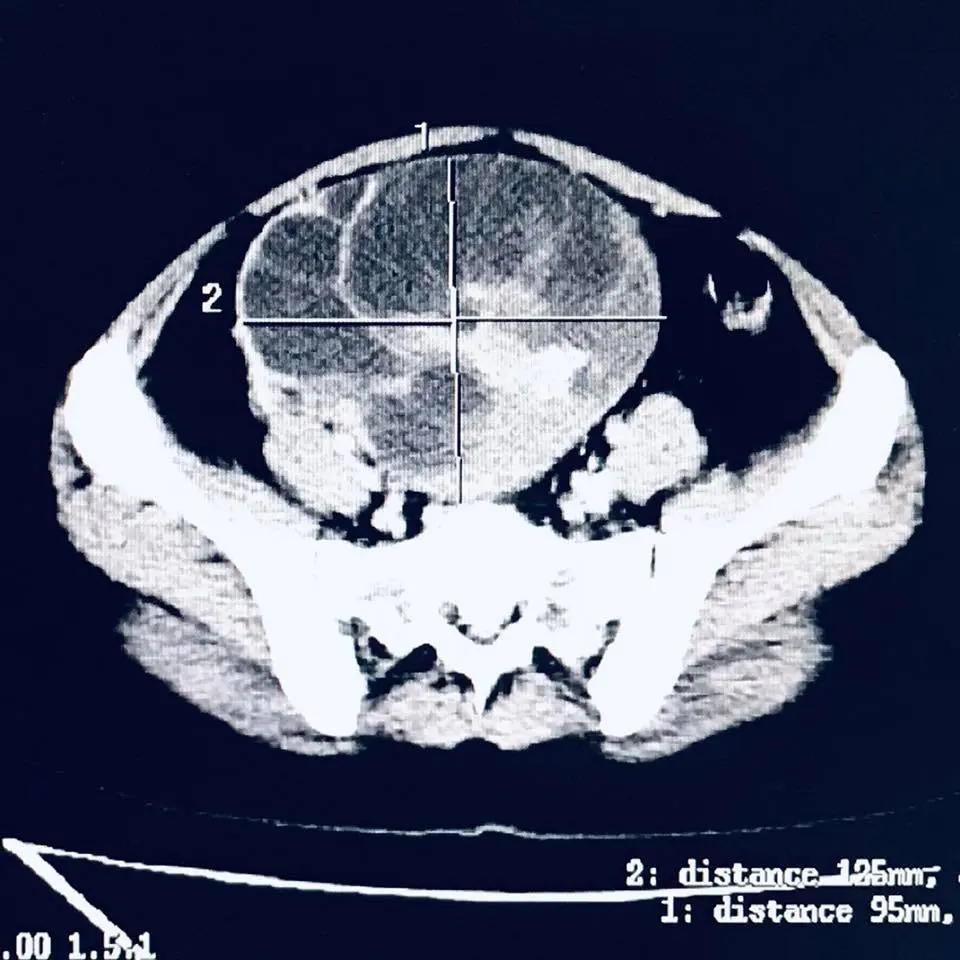

ทำไมวันนี้ถึงโตเบ้อเริ่มเลยหล่ะ_ผมจึงขอคิวด่วนกับรังสีแพทย์เพื่อตรวจเอ็กซ์เรย์คอมพิวเตอร์ : สรุปว่าผู้ป่วยมีถุงน้ำรังไข่โตขึ้นมาก จาก4ซม. เป็น 12.5 x 9.5 ซม. ในช่วงเวลาสองเดือนเองนะครับ

ผลการตรวจเอ็กซ์เรย์คอมพิวเตอร์_พบว่าถุงน้ำนี้กดเบียดท่อไตด้านขวาด้วยครับ ตอนนี้ไตด้านขวาของผู้ป่วยบวมมากเนื่องจากปัสสาวะไหลมาทางท่อไตไม่ได้แล้ว จึงทำให้ปัสสาวะคั่งค้างในไต

จากภาพเป็นถุงน้ำรังไข่ชนิดที่เรียกว่า มิวซินนัส (mucinous) ครับ เกิดขึ้นมาจากเยื่อบุผิวของรังไข่ ลักษณะภายนอกมักเป็นถุงน้ำขนาดใหญ่ ภายในประกอบด้วยถุงนำ้หลายถุง ผิวเรียบ ผนังหนาขุ่น ภายในถุงน้ำบรรจุน้ำเมือกเหนียว ส่วนใหญ่จะพบแค่ข้างเดียว